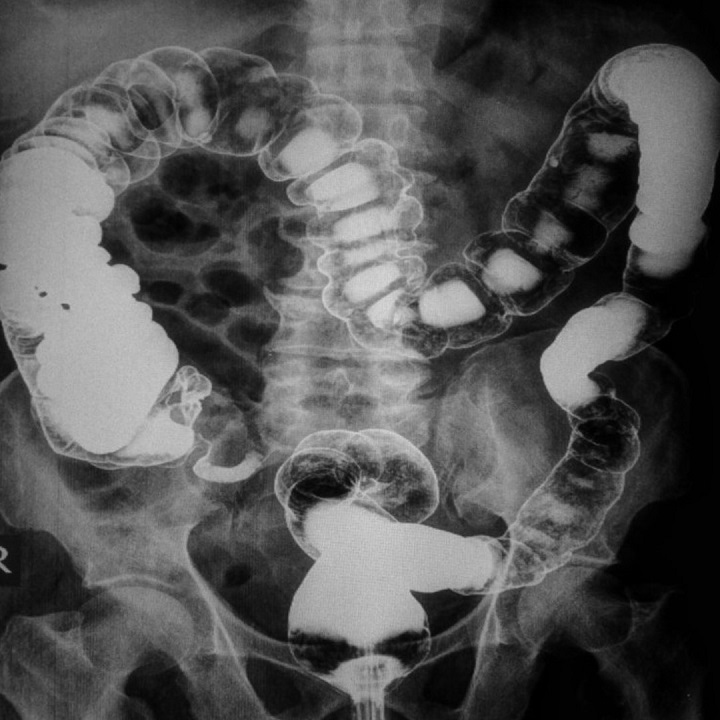

Bármi is okozza a gyakori puffadást, hasmenést, hányingert, teltségérzetet, görcsöket, élesebb hasi fájdalmakat, azt jelzi, hogy valami nem megfelelően működik a szervezetben, amit orvosolni kell. Sok esetben a tünetek "csak" kellemetlenek, a veszélyes az lehet ha összefüggnek betegségekkel.